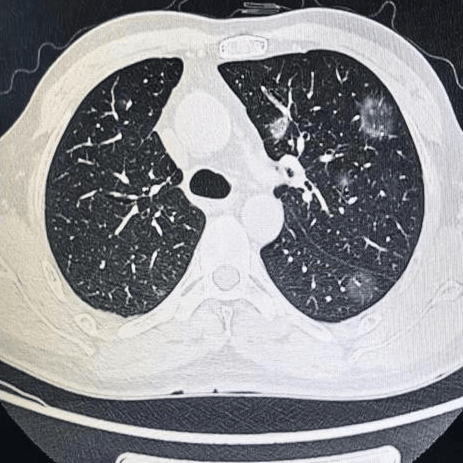

肺结节是指影像学表现为最大径 ≤ 30mm的局灶性、类圆形、较肺实质密度增高的实性或亚实性阴影,可为孤立性或多发性,不伴肺不张、肺门淋巴结肿大和胸腔积液。

多种多样的肺部小结节